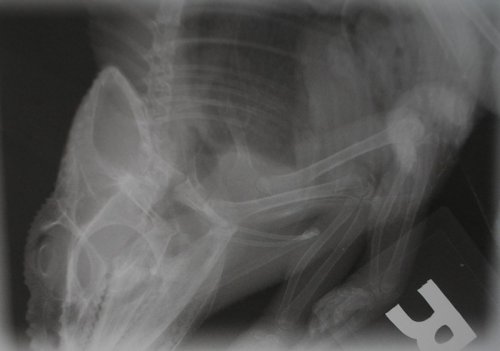

Well I made it to the vet yesterday and took some pictures of the xrays. Conditions weren't all that great and my camera was not cooperating, this is the best I got of the three xrays that were done intially.

head.JPG

whole body top.JPG

whole body side.JPG

The film for the last one was extremely dark and you can see the reflection in the photos, that is the best I was able to get.

While in the process of removing the skin I felt something that made me cringe. Anyone that have ever had a broken bone know what I am taking about. The feeling of bone sliding on bone. It was on his right side, basically where the first ribs that connect to their "sternum", dunno if its the same for them. I palpated a little more and felt it again, I also noticed considerable deflection of the area when compared to the other side. So I head to the vet with a pretty good idea of where and what to look for in the xrays, but as you just saw the angles were not very good for viewing that area.

A few more were taken however we were not able to get a clear enough picture of that area to make a definitive diagnosis. Pictures were taken of all of them xrays, 7 views in total, and sent out to another expert. I was supposed to get the same email with the photos but there must have been an issue with the mail servers. When I do get the pics Ill post them as well.